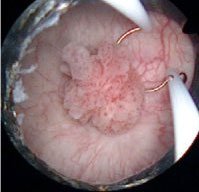

Şekil: TUR-M işlemi başlangıcında tümörün görüntüsü.

Trans-Üretral Rezeksiyon-Mesane (TUR-M): Mesane tümörü patolojik tanı ve tedavisinde ilk ve en sık uygulanan yöntemdir. Bu yöntemde, işeme kanalı içerisinden idrar kesesine kamera ve kesme işlemini gerçekleştirmemizi sağlayan ekipmanlar bulunan aletle girilmekte böylede hem mesane içerisindeki tümörü görüntülemekte hem de tümörü keserek tedavisini sağlamaktayız.Operasyonda kullanılan aletler kullanılan enerji kaynakları ve solüsyonların değişmesi ile birlikte monopolar, bipolar plazmakinetik gibi farklı isimlerle adlandırılmaktadır. Ancak tüm bu isim farklılıklarına rağmen yapılan işlem onkolojik başarı anlamında birbirine üstünlükleri yoktur. Bu teknolojik değişikliklerin birbirine üstünlükleri operasyon süresini kısaltma, işlemi gerçekleştiren hekiminin daha az kanama kontrolü ile uğraşması, daha net bir görüntü altında işlemi tamamlaması gibi birtakım avantajları vardır. Bu açıdan saydığımız teknolojik değişiklerden en avantajlı plazmakinetik ile yapılan TUR-M işlemidir. İşlem süresi tümör büyüklüğüne, tümörün yerine, kanamaya bağlı olarak 5-10 dk dan 1-2 saate kadar sürebilmektedir. Hasta genellikle operasyondan 1 gün sonra taburcu olabilmektedir. Operasyon sonrası takılan sondada yine kesilen dokunun derinliği ve yaygınlığına göre 1 ile 7 gün arası tutulabilmektedir.